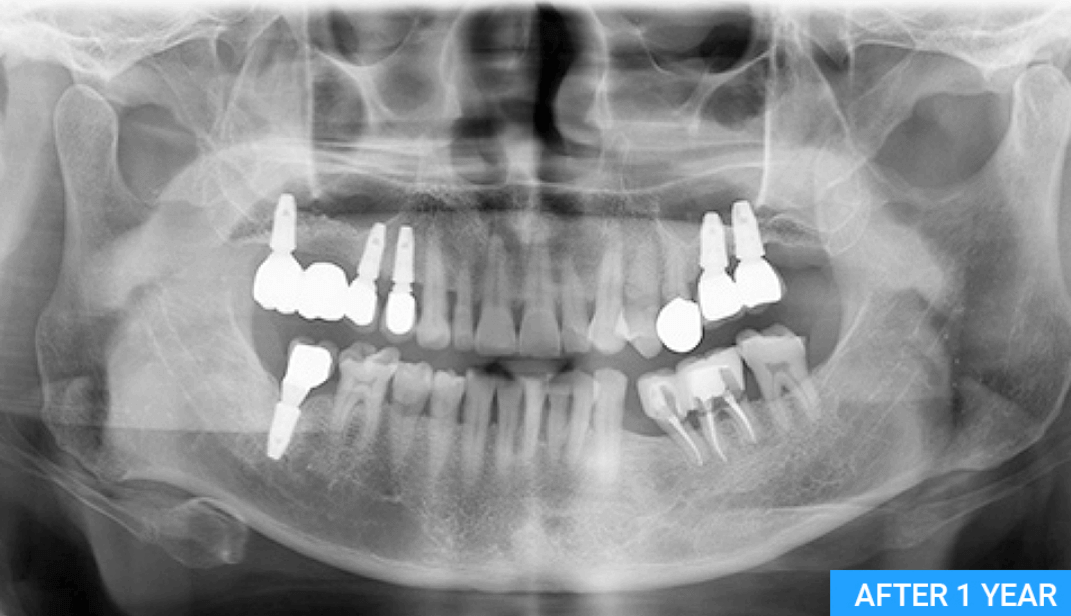

치아 엑스레이를 보면 치열이 변하여 임플란트를 하고 나서도 교정이 필요할 수 있습니다. 치아교정은 시간도 오래 걸릴 뿐만 아니라 임플란트 비용보다 교정 비용이 더 비싸고 오래 걸립니다.